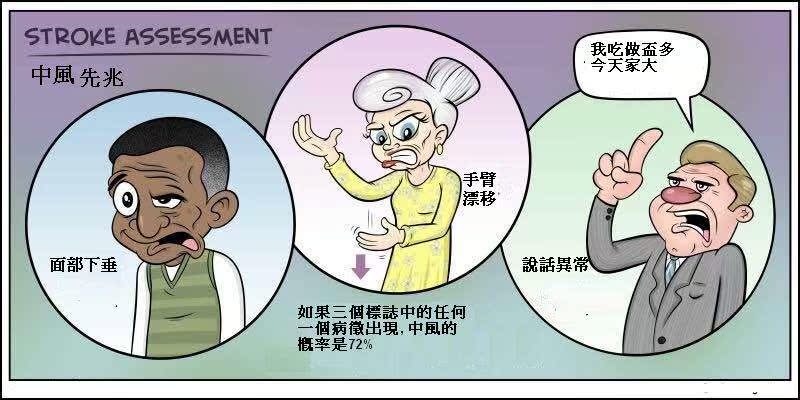

3、中风先兆:

突然出现睡觉流口水,晨起后自己最好对着镜子笑一笑,如果伴有口角歪斜或头疼等症状,就意味着中风的可能性比较大,此种情况下,切不可掉以轻心,应立即到医院进行相关检查,防患于未然。